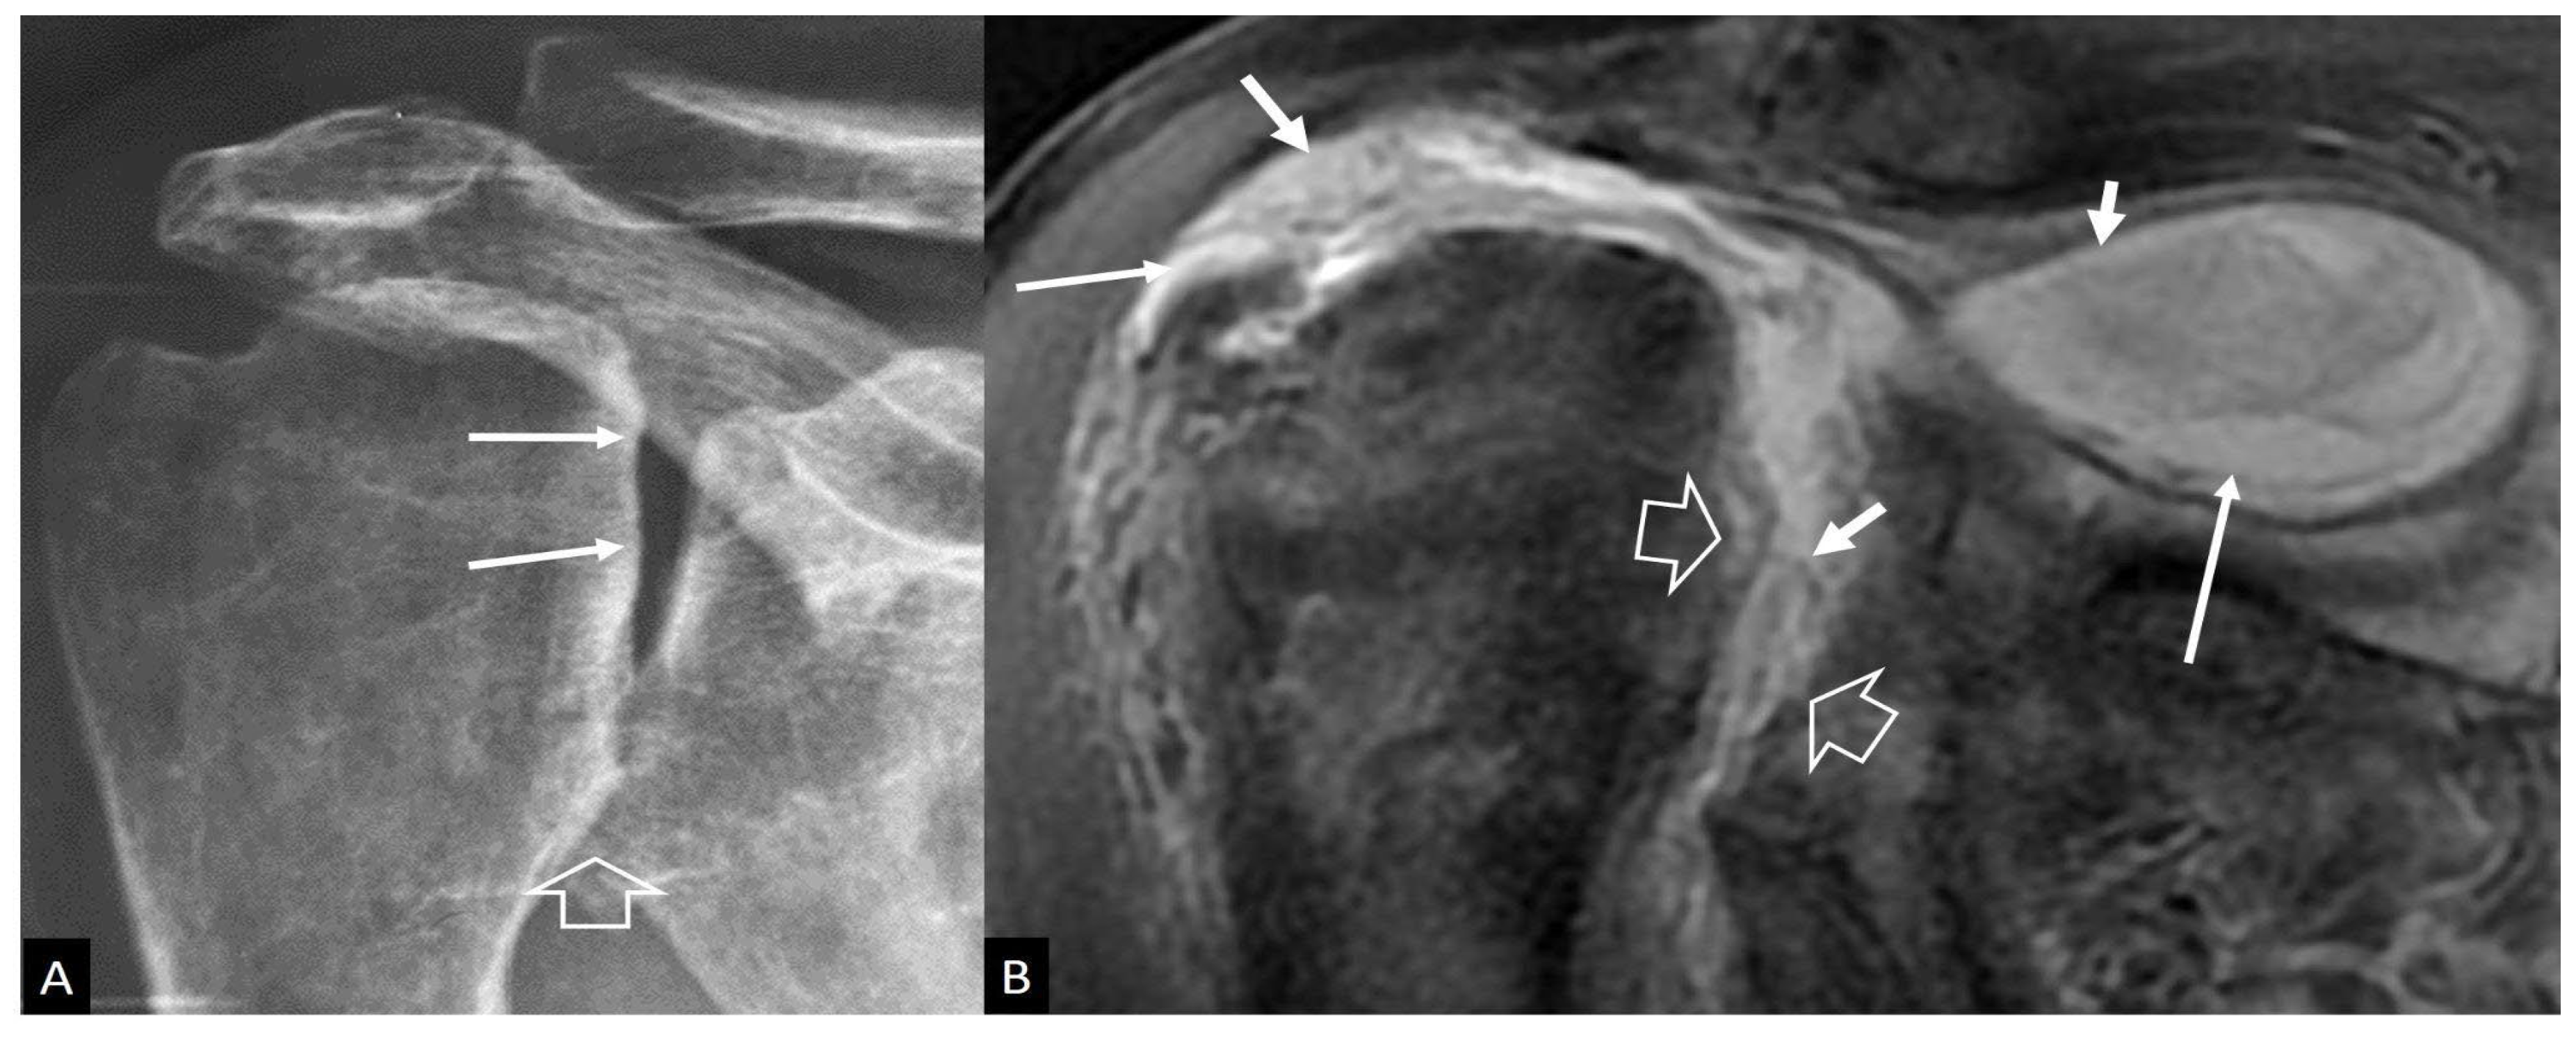

3. b.iv. Rapidly Destructive Osteoarthritis of the Hip

3. b.v. Neoplasms